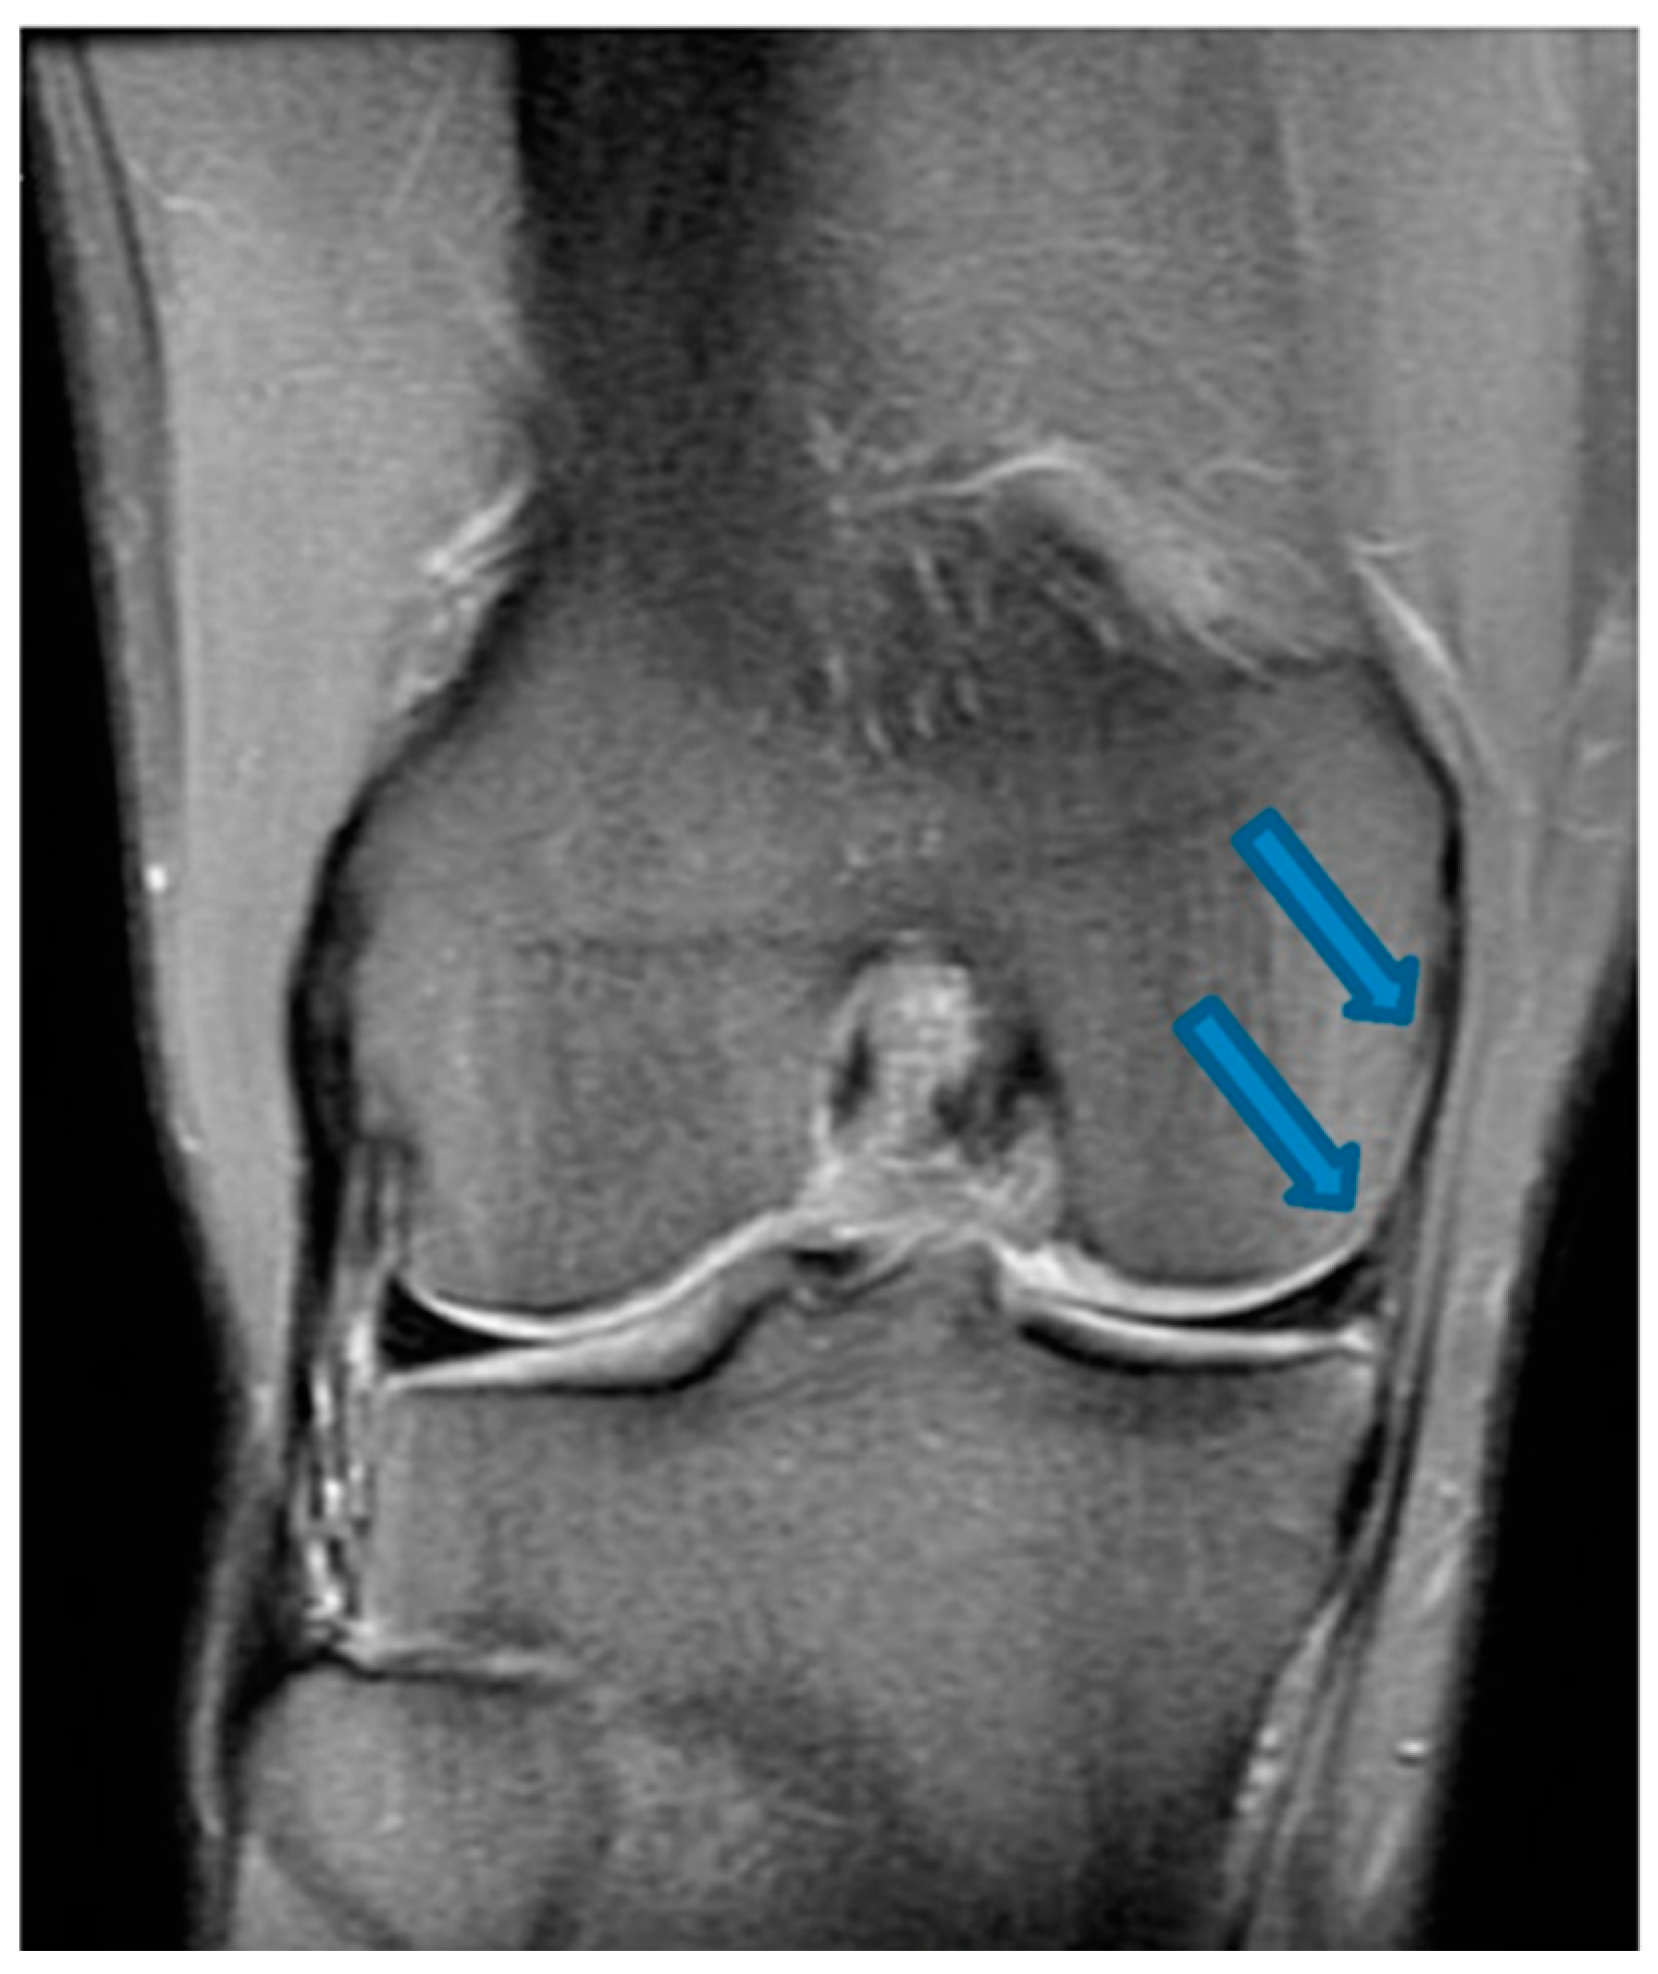

| 9 November 2020 | MRI scans demonstrating signs of partial ACL healing |

| 14 August 2021 | MRI scans demonstrating signs of complete ACL healing |

| 24 December 2021 | MRI scans confirming signs of complete ACL, MCL and medial meniscus healing |